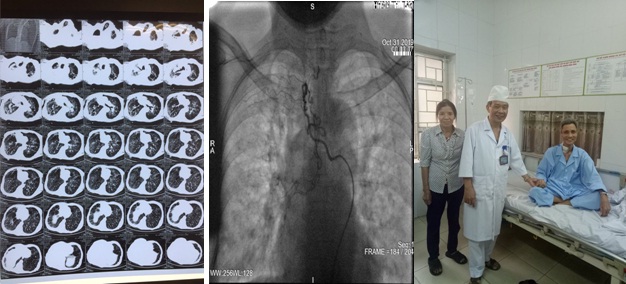

Các bác sĩ Trung tâm Nội Hô hấp, Bệnh viện Quân y 103 vừa cấp cứu thành công một bệnh nhân nam 62 tuổi, ở Vĩnh Tường, Vĩnh Phúc, bị ho ra máu mức độ rất nặng.

Cụ ông vừa được cứu sống. (Ảnh: Chí Tuấn - SKĐS)

Bệnh nhân chuyển tới Trung tâm Nội Hô hấp, Bệnh viện Quân y 103 trong tình trạng thể trạng suy kiệt nặng (35kg/158cm), gù vẹo cột sống, 2 phổi bị xơ, giãn phế quản nặng. 22 giờ ngày 30/10/2019, bệnh nhân đột ngột ho máu số lượng khoảng 600ml màu đỏ tươi, biểu hiện suy hô hấp: tím tái, huyết áp tụt.

Các bác sĩ đã nhanh chóng khai thông đường thở, đặt ống nội khí quản, thở máy và ngay lập tức kích hoạt kíp trực can thiệp mạch cấp cứu. Sau 3 giờ can thiệp, bệnh nhân được chuyển về Trung tâm Hồi sức cấp cứu tiếp tục theo dõi. 2 ngày sau bệnh nhân được rút ống nội khí quản, ý thức và vận động hoàn toàn bình thường, bệnh nhân chỉ khạc ít đờm lẫn máu cũ.